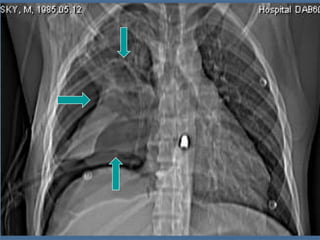

RUPTURA TRAUMÁTICA DE LA AORTA

RX DE TORAX:

1. ENSANCHAMIENTO DEL MEDIASTINO.

2. BORRAMIENTO DEL BOTON AORTICO.

3. DESVIACION DE TRAQUEA A LA DERECHA.

4. BORRAMIENTO DE LA VENTANA AORTOPULMONAR.

5. DEPRESIÓN DEL BRONQUIO IZQUIERDO.

6. DESVIAICIÓN DEL ESÓFAGO A LA DERECHA.

7. ENSANCHAMIENTO DE LA FRANJA PARATRAQUEAL.

8. ENSANCHAMIENTO DE LA INTERFASE PARAVERTEBRAL.

9. GORRO PLEURAL

10. HEMOTÓRAX IZQUIERDO.

11. FRACTURA DE 1A. O 2A. COSTILLAS O DEL OMOPLATO.

AORTOGRAMA